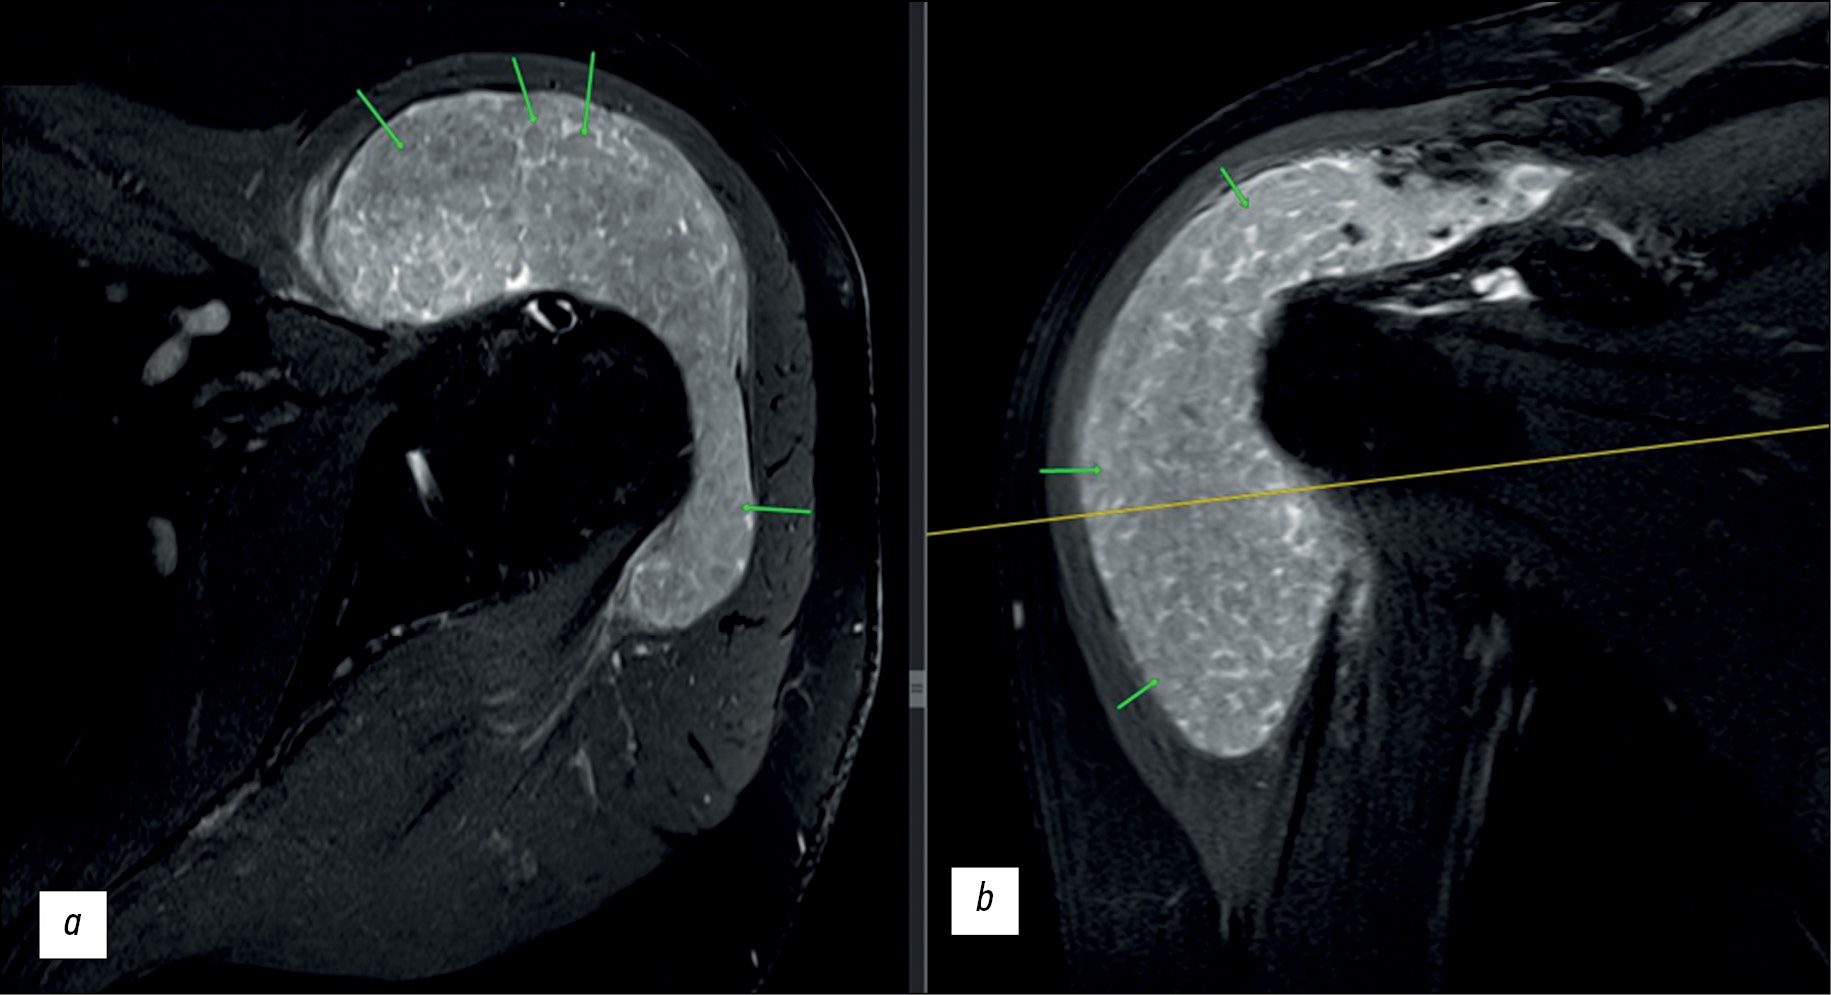

Under the deltoid, inside the subacromial bursa and subdeltoid bursa enlarged to the size of 7.7 × 2.5 × 5 cm, T2-weighted imaging (WI) showed multiple similarly shaped oval structures measuring 2–3 mm to 8–10 mm in diameter with an intermediate signal intensity, separated by areas of increased signal intensity (in T2-WI). In T1-WI, these structures demonstrated homogeneous intermediate signal intensity (Figs. 1 and 2). Agglomerations of small inclusions resembled space-occupying masses in the joint cavity.

Fig. 2. Magnetic resonance imaging of the left shoulder joint, T2-weighted images with signal suppression from fat: a - transverse section; b — frontal section. Small structures within the bursae are indicated by arrows.

In MRI, rice bodies are visualized as multiple small, similarly shaped, rounded structures. In T1-WI, they are isointense or hypointense; in T2-WI, they are hypointense. The T2-WI pattern in the described case consisted of densely agglomerated inclusions, which were hyperintense compared with the muscle tissue, which is typical in RA. As demonstrated in the case presented, MRI is superior to CT in identifying rice bodies.